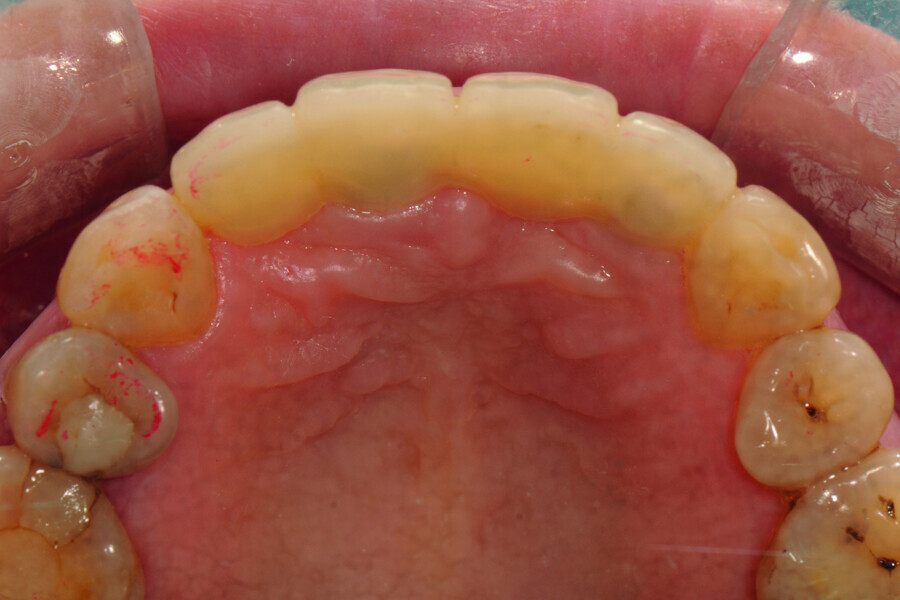

Fig. 6: Occlusal view of the anterior teeth immediately post-op.